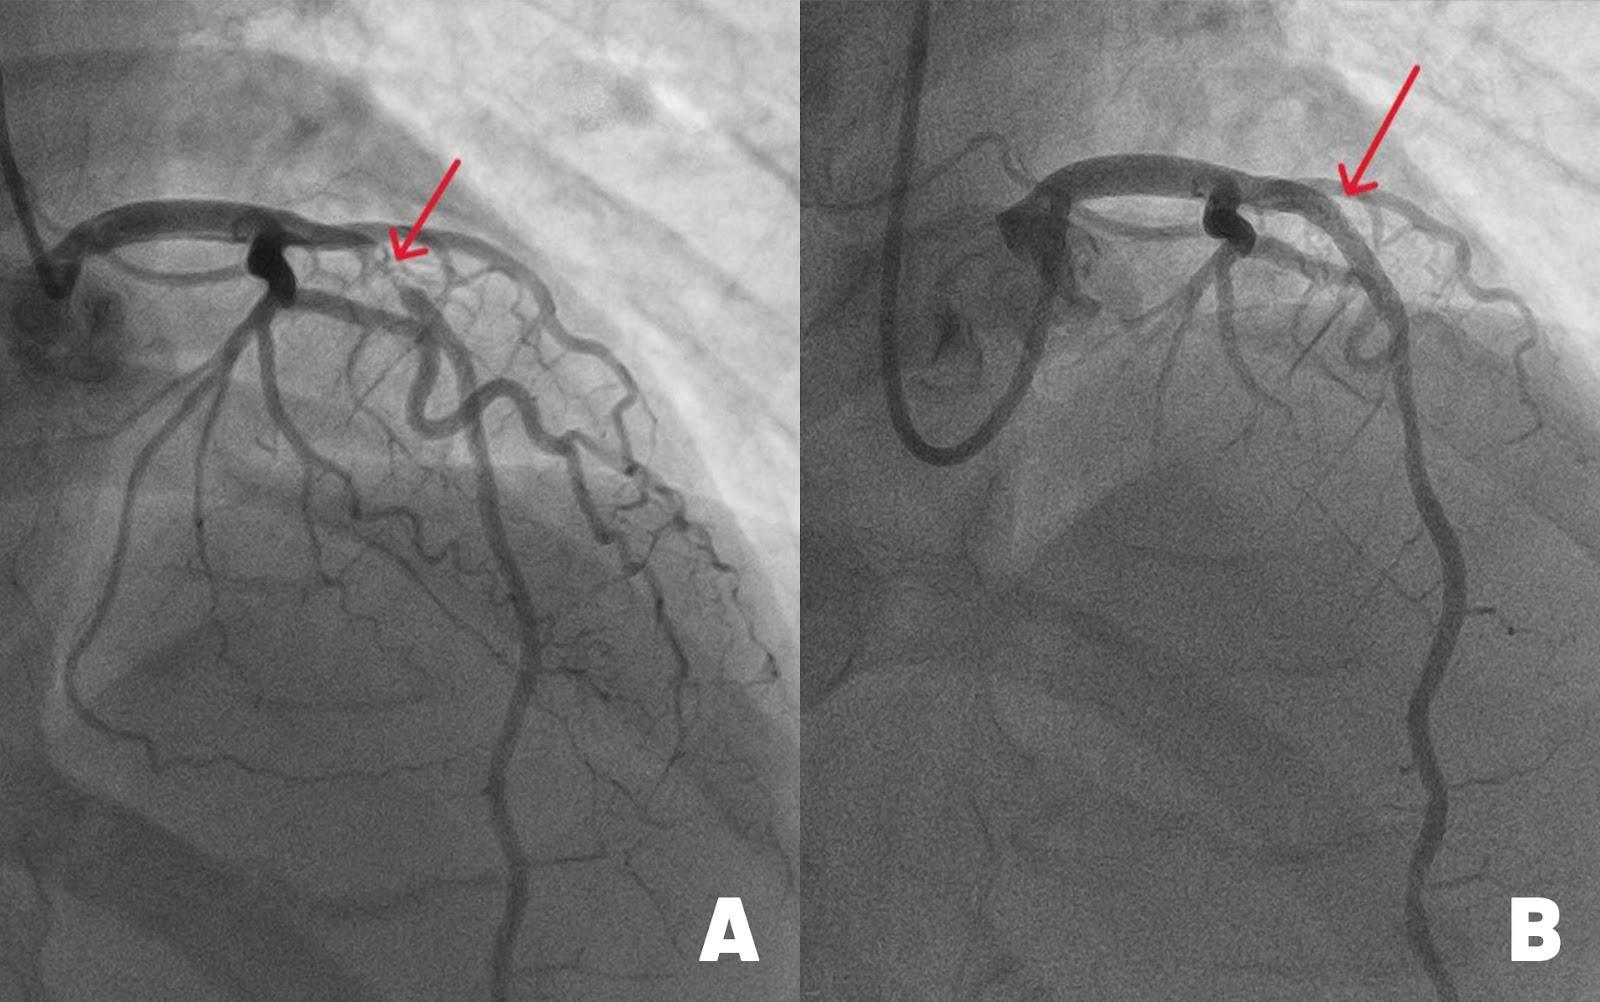

Hình ảnh động mạch liên thất trước (mạch máu chính nuôi tim) bị đứt do tắc nghẽn nặng (hình A) và sau khi được tái thông nhờ đặt stent kích thước lớn. Ảnh: BVĐK Tâm Anh

Kết quả chụp mạch vành cho thấy, động mạch liên thất trước hẹp đến 99%. May mắn là vẫn có một dòng chảy nhỏ giúp cầm cự, tưới máu tạm thời nuôi cơ tim. “Với tình trạng này, cần can thiệp đặt stent càng sớm càng tốt cho bệnh nhân để tái thông dòng máu, tránh nguy cơ đột quỵ tim có thể xảy đến bất cứ lúc nào”, bác sĩ Long cho biết.

Với kinh nghiệm xử lý những ca hẹp nặng mạch vành, bác sĩ Long và êkip luồn ống thông từ động mạch quay (ở cổ tay) tới chỗ xuất phát động mạch vành trái. Sau đó, luồn sợi dẫn 0.35mm qua vị trị hẹp ở động mạch liên thất trước. Dưới sự hỗ trợ của hệ thống siêu âm trong lòng mạch (IVUS), êkip đo đạc chính xác đường kính mạch máu, đặt một stent phủ thuốc, nong nở rộng lên đến 4.0 mm, áp sát thành mạch, ngăn nội mạc mạch máu tăng sinh quá mức. Điều này giúp giảm nguy cơ tái hẹp trong stent, tái phát nhồi máu cơ tim xuống thấp (dưới 2%).